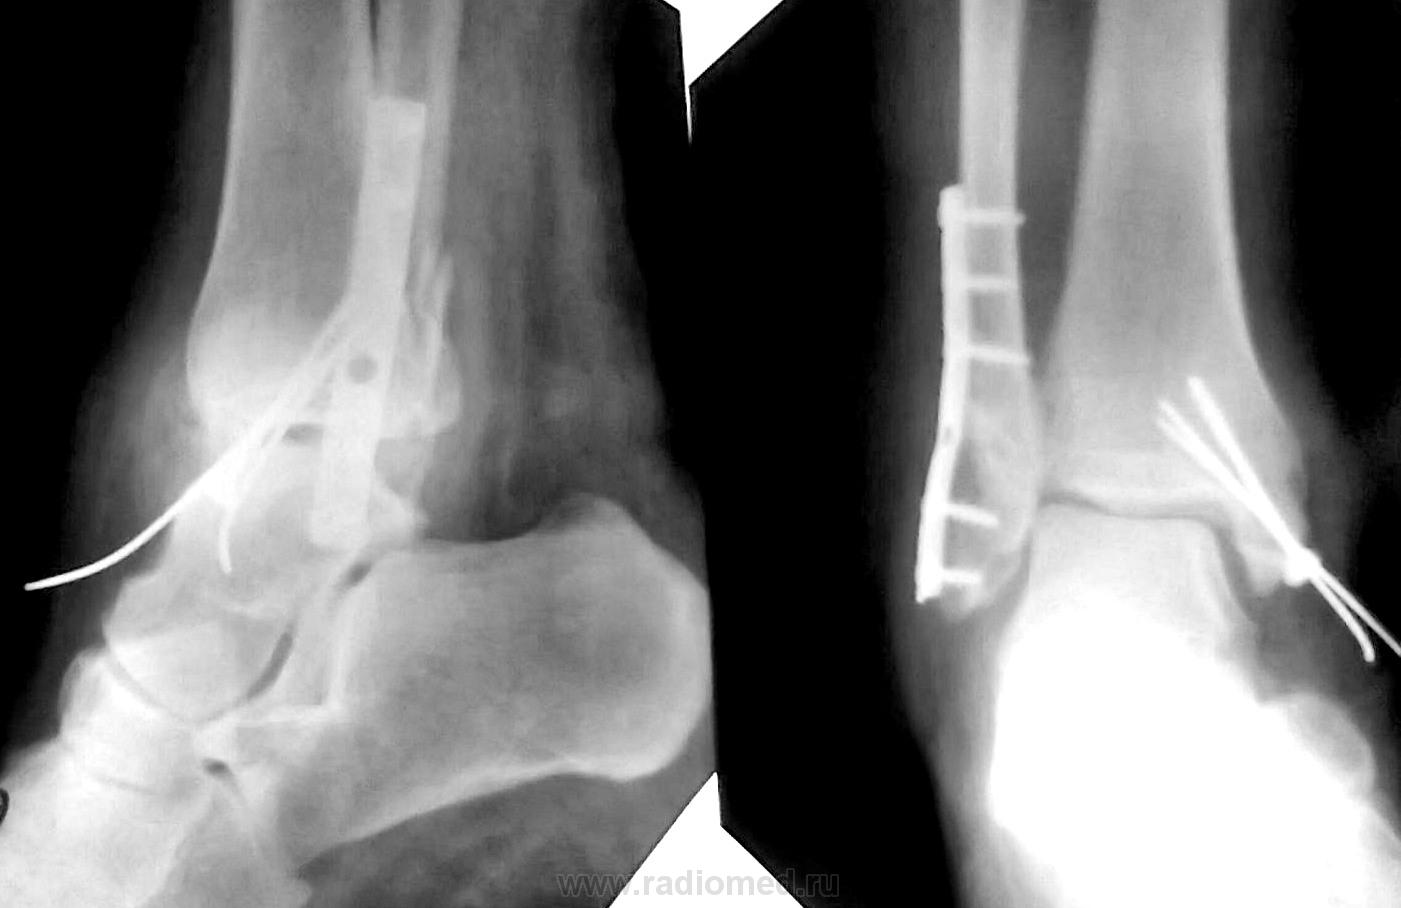

Пациентке 50 лет, в марте 2011 получила бытовую травму, при поступлению в одну из ЦРБ Нижегородской области был диагносцирован трехлодыжечный перелом, наружный подвывих стопы (рентгенограммы 1). Поскольку боковая рентгенограмма сделана с ротацией, никто не обратил внимания на передний отдел метаэпифиза б/берцовой кости. Пациентке налажено скелетное вытяжение (рентгенограммы 2,3), на боковом снимке видно повреждение переднего отдела метаэпифиза, но внимание на это не обращается, выполняется стандартный остеосинтез наружной и внутренней лодыжек (рентгенгограммы 4), опять же ни о кого не возникает никаких вопросов, а именно: почему дисконгруэнтна суставная щель, стопа в переднем подвывихе и в эквинусе. В августе пациентка приходит на контроль, и уже отчетливо виден дефект переднего отдела метаэпифиза б/берцовой кости, смещение костного фрагмента метаэпифиза кпереди и передний вывих стопы, но никаких мероприятий не проводится. Вчера, 9.02 пациентка все же доходит до нашего института, и мы видим такую картину (рентгенограммы 5,6): дефект переднего края дистального метаэпифиза б/берцовой кости, костный фрагмент смещен кпереди, некротизирован (фактически это секвестр), стопа в положении переднего вывиха, разрыв дистального межберцового синдесмоза, нестабильность металлоконструкций в б/берцовой кости (отчетливо видна резорбция), асептический некроз блока таранной кости. Прогноз неблагоприятен: артродезирование г/стопоного сустава, вопрос только в выборе метода, аппаратный артродез, либо ретроградный интрамедуллярный.

Передний край разъехался,  и после изображения 7 не устранен подвывих стопы кпереди. Плюсом наверняка несоблюдение режима и рекомендаций. Думаю, ортопеды поправят, если не права, но мне кажется, тут нужно было при первичном остеосинтезе фиксировать межберцовый синдесмоз... да и на метафиз б/б кости тоже винт с шайбой, наверное. Сейчас как собирать такое - очень непростая задачка+воспаление.

Не выполнен стяжной болт. В результате росхождение ДМС.

Уважаемые коллеги. Перелом отнюдь не краевой, а костный фрагмент был достаточных размеров. Подозреваю, что его  ошибочно посчитали  фрагментом заднего края. Остеомиелита ни клинически, ни рентгеологически не было. Даже если бы этот перелом и не был фиксирован, он мог бы сростись без дополнительной накостной фиксации, если бы стопа была выведена из переднего подвывиха и эквинуса, и иммобилизирована в положении тыльного сгибания. На данный момент помимо обширного дефекта переднего края есть и явления ассептического некроза блока таранной кости, восстановительная операция не показана, только артродез.

Боковой снимок при поступлении сделан с ротацией, это было одной из причин того, что пропустили перелом пилона, сказать по этой рентгенограмме о положении стопы затруднительно.